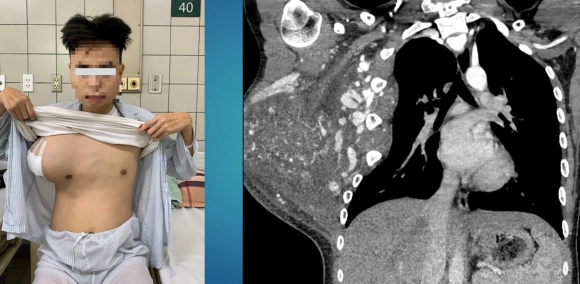

Bệnh nhi vượt qua ca phẫu thuật nhiều khó khăn, gần như thay máu toàn bộ cơ thể (Ảnh: H.Hải).

Ths.BS Ngô Gia Khánh, Trưởng khoa Phẫu thuật lồng ngực - mạch máu thông tin, bệnh nhân được đưa đến Bệnh viện Bạch Mai hôm 24/2, trong tình trạng có khối u khổng lồ lồng ngực, tăng sinh nhiều mạch máu.

Khối u kéo lệch lồng ngực, ăn rộng ra bả vai (Ảnh: Bệnh viện cung cấp).

"Khi tiếp nhận bệnh nhân, chúng tôi cũng bất ngờ bởi một khối u khủng chiếm trọn một bên ngực, ăn rộng, xâm lấn ra xương bả vai, chèn ép vào thành ngực. Đặc biệt, khối u tăng sinh mạch máu rất nhiều, để xử lý sẽ có nguy cơ chảy máu ồ ạt", BS Khánh thông tin.

Sau ca mổ đầy khó khăn, các bác sĩ đã lấy ra được khối u thành ngực nặng hơn 3kg. Kết quả giải phẫu bệnh sau đó cho thấy là bệnh u mạch trong cơ, đây là tổn thương lành tính rất hiếm gặp, chiếm 0,7% các ca bệnh lành tính ở thành ngực.

Trên thế giới, một số trường hợp có khối u tương tự đã được báo cáo dưới dạng các ca lâm sàng, tuy nhiên, không ca nào ghi nhận khối u kích thước lớn như trường hợp này.